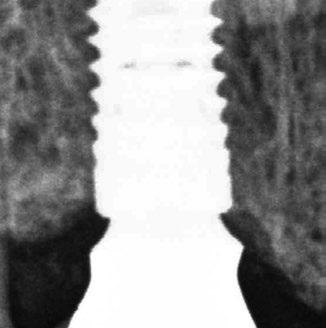

Az eljárást helyi érzéstelenítés mellett végeztük (4%-os articaine-hidroklorid 1:100 000 adrenalinnal). Papillakímélő, U alakú palatális bemetszést végeztünk, teljes vastagságú nyálkahártyalebeny preparálás történt, a lebenyt bukkálisan feltekertük (5. ábra). A lebeny bukkálisan feltekert részén de-epitelizációt végeztük el, amellyel kompenzálni tudtuk a bukkális lágyszöveti defektust. Szakaszos előfúrást végeztünk, és a bredent copaSKY 4x10 implantátumot 30 Ncm behajtási nyomatékkal helyeztük be (6. ábra). Az implantátumot 1 mm-re szubkresztálisan helyeztük be, hogy később szélesebb emergenciaprofilt tudjunk kialakítani (7. ábra). Az egyedi ínyformázó úgy készült, hogy kompozitot vittünk fel a titánbázisra, és így formáztuk a lágyszöveteket a transzgingivális gyógyulási fázis során (8. ábra). Az egyéni ínyformázó tulipán formájú, hogy kialakítsa a kívánt emergenciaprofilt. A lágyszövetet feszülésmentesen zártuk #6/0 nem felszívódó, monofil fonallal (Optilene, B. Braun Deutschland; 9. a–b. ábra). Posztoperatív röntgenfelvétel készült, ami alapján az implantátum a szomszédos fogakkal párhuzamos elhelyezést mutatott (10. ábra). Posztoperatív utasításokat adtunk a páciensnek a műtéti terület körüli szájhigiénia fenntartása érdekében. A beavatkozást követő egy héttel a varratokat eltávolítottuk, és a kezelt terület kielégítő gyógyulást mutatott (11. ábra). A 4 hónap utáni késleltetett terhelést a páciens kívánsága szerint terveztük.

10. ábra: A műtét utáni radiológiai felvétel.